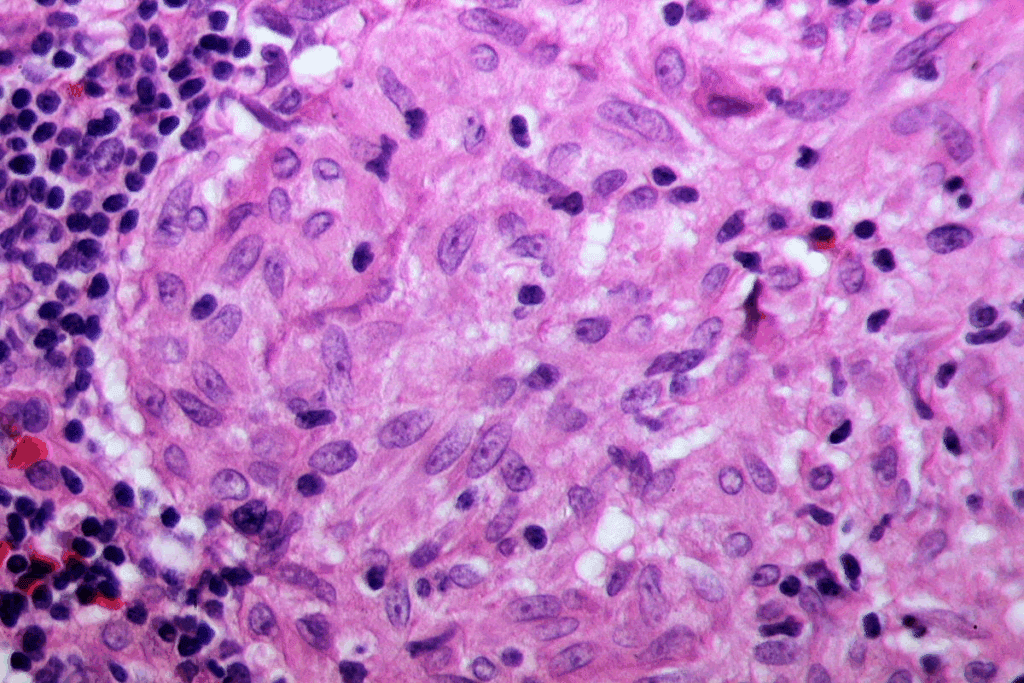

Biopsy Procedures and Tissue Analysis

A biopsy takes a tissue sample from the area that looks odd. This is key to finding out if cancer cells are there.